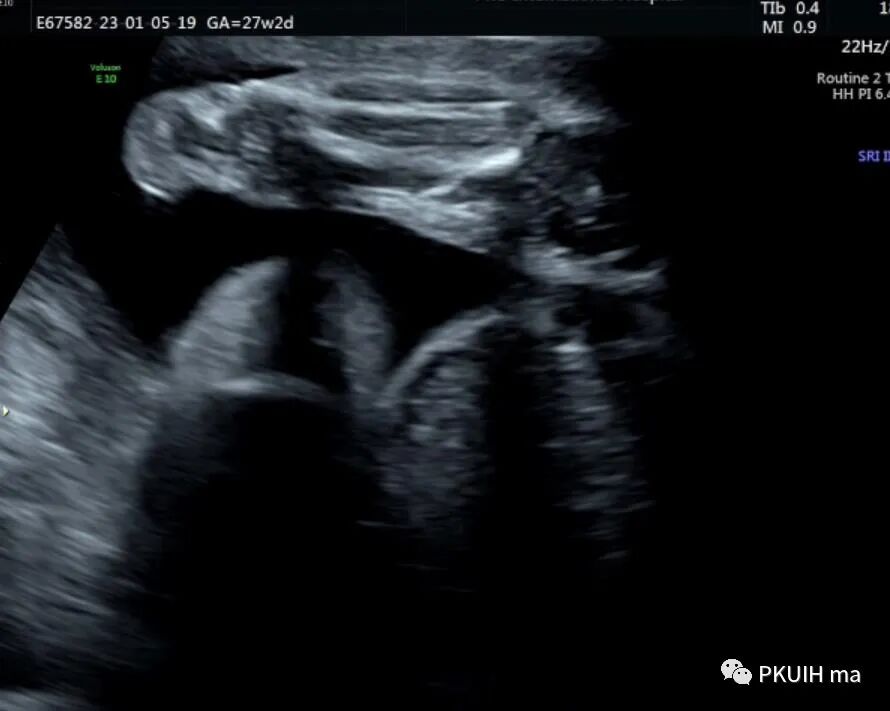

孕妇26岁,G2P0,发现胎儿肢体异常来诊,目前孕27周,超声图像如下:

四肢长骨均短缩、弯曲成角,Z值小于-4,孕妇自述第一胎也是肢体明显短,最后在当地医院引产,未做其他相关检查,本次怀孕又发现胎儿肢体短,因此来京咨询并做相关检查。

3、长骨弯曲度  目前没有客观方法来评估长骨弯曲度,多依靠经验来辨别。股骨弯曲或成角(肢体屈曲)是肢体屈曲症、致死性侏儒、成骨不全、短肋发育不良和低磷酸酯酶症的特征。